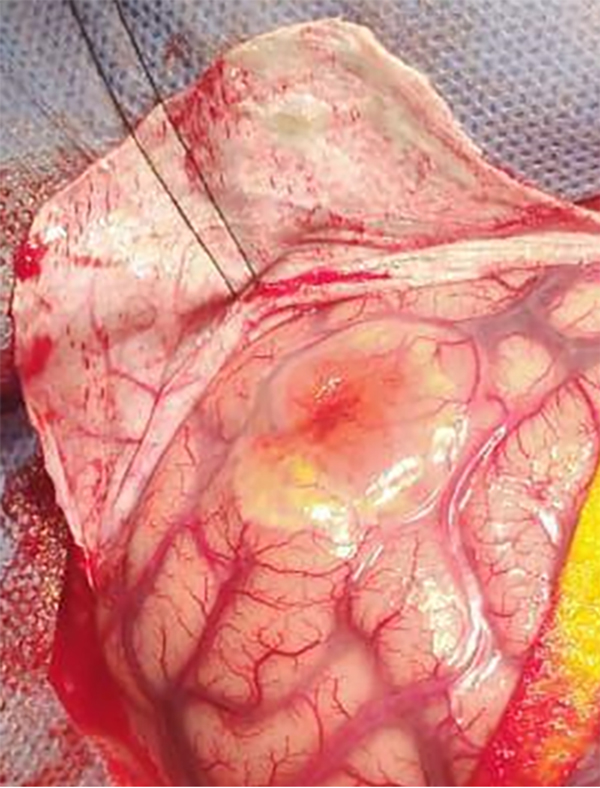

Paciente de 14 años, previamente sano, consulta en guardia externa de hospital de cercanía por episodio de afasia de expresión seguido por convulsión tónico clónica generalizada con periodo postictal que requiere intubación orotraqueal y derivación a UTIP de Hospital de Niños Ricardo Gutiérrez para complementar estudios. Se realiza tomografía computada (TC) de cerebro simple y en el informe preliminar no se evidencian alteraciones significativas. Se procede a la extubación electiva y posterior pase a sala de Clínica Médica. Se realiza resonancia magnética (IRM) de cerebro con y sin contraste donde se observa lesión extraaxial de bordes definidos a nivel parietal izquierdo que contacta con el giro angular, de 29 mm. de diámetro anteroposterior, 15 mm de diámetro transverso y 20 mm de desarrollo cefalocaudal. La lesión restringe en la técnica de difusión. En el T2 se evidencian imágenes con vacío de flujo evidenciando estructuras vasculares. El examen no demuestra lesión ósea. El refuerzo postcontraste es franco aunque heterogéneo y no presenta realce dural adyacente a la lesión. (Fig. 1). En la TC simple de cerebro, en ventana ósea, no se evidencia reacción periostica perilesional.

Figura 1: IRM de cerebro con y sin contraste, A) T1 C + Axial. Lesión extra axial a nivel del giro angular, se observa refuerzo tras la administración de gadolinio B) T2 Axial. Se evidencia edema perilesional vasogénico C) DWI ADC Axial. Tumor que restringe a la técnica de difusión.